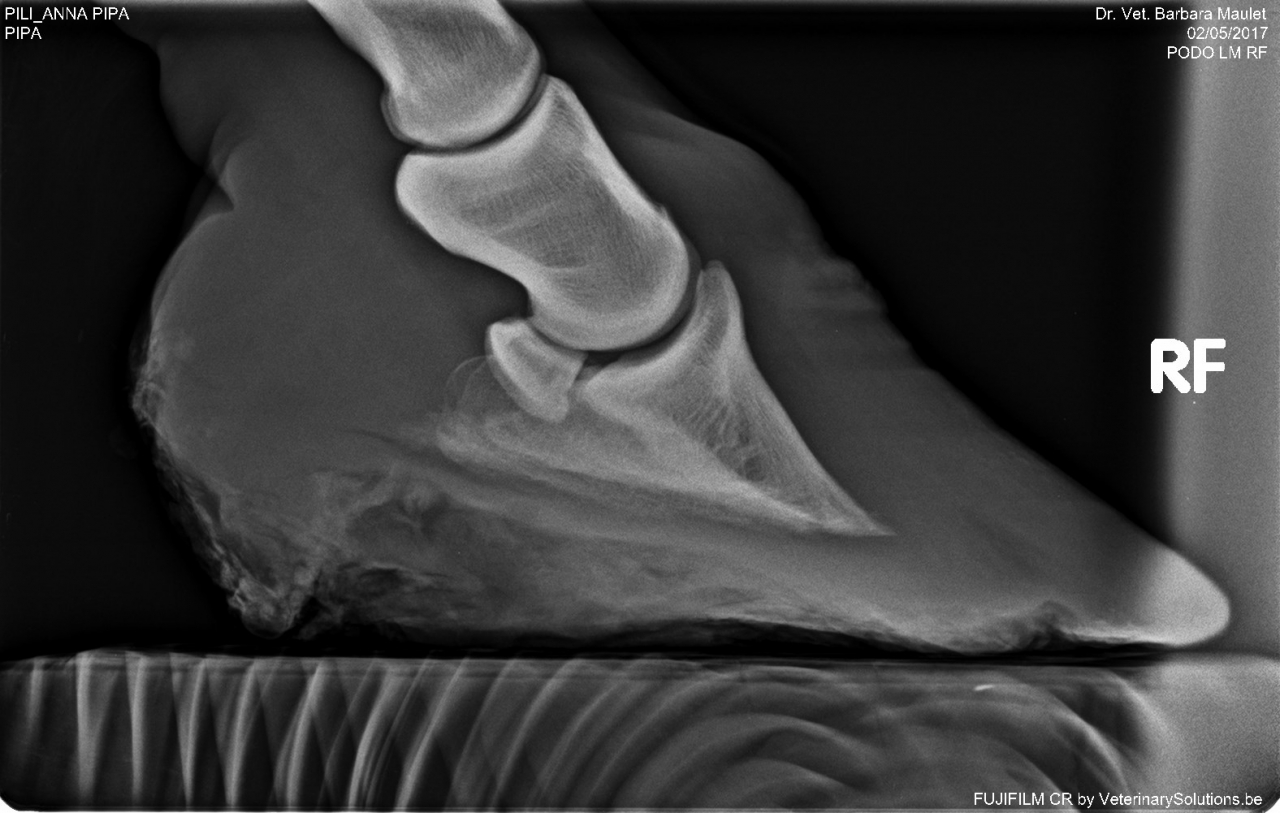

DéconnectéDire merci | j'ai fait piquer mardi la petite fourbue juste après avoir vu ses radios pour mémoire la photo: ![]() à des fins didactiques les radios ![]() ![]() non seulement il y a bascule totale de la phalange mais un gros remodelage de l'os, y avait rien à récupérer. Pipa la jument de manège a aussi été fourbue plusieurs fois, elle ne marche pas correctement des 2 antérieurs. son taux d'ACTH est à 96 ce qui ne me semble pas énorme. Les radios: ![]() ![]() basculement présent mais nettement moins important, léger remodelage. Rassurez vous le MF est passé hier ... |

| Dire merci | Les radios font froid dans le dos 😔 Bon voyage à cette petite 🌈 |

| Dire merci | les radios de la petite fourbue ![]() Elle aura au moins connu un peu de réconfort dans sa fin de vie et aura évité de longues semaines (mois, années ?) de souffrance supplémentaires |